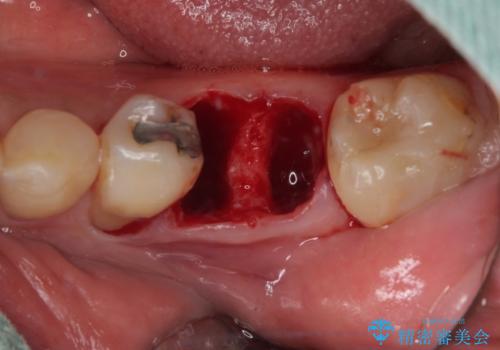

下顎大臼歯の抜歯即時埋入インプラント治療では、複数ある歯根のうち、後方の歯根部にインプラントを埋入することで一般的であり、今回破折して骨吸収が著しいのは前方の歯根であったため、事前に仮歯を用意した上で、抜歯即時埋入インプラントによる補綴治療を行うこととしました。

来院されるまではインプラント治療を躊躇されていましたが、抜歯即時埋入により、単回の外科処置で治療が終えられることのメリットを理解され、インプラントによる補綴治療を行いました。

スムーズに治療を終えることができました。